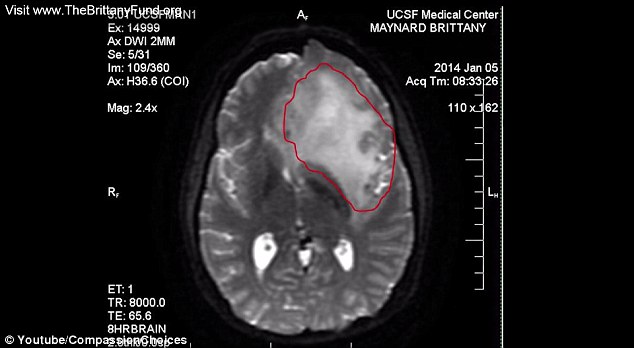

Brittany is suffering from stage 4 Brain Cancer.

In January, doctors told her she had stage 2 Brain Cancer. They gave her 3-10 years to live.

But then in April, the news got even worse. Her cancer was now stage 4. (The worst it can get)

Doctors told her she now only had 6 months to live.